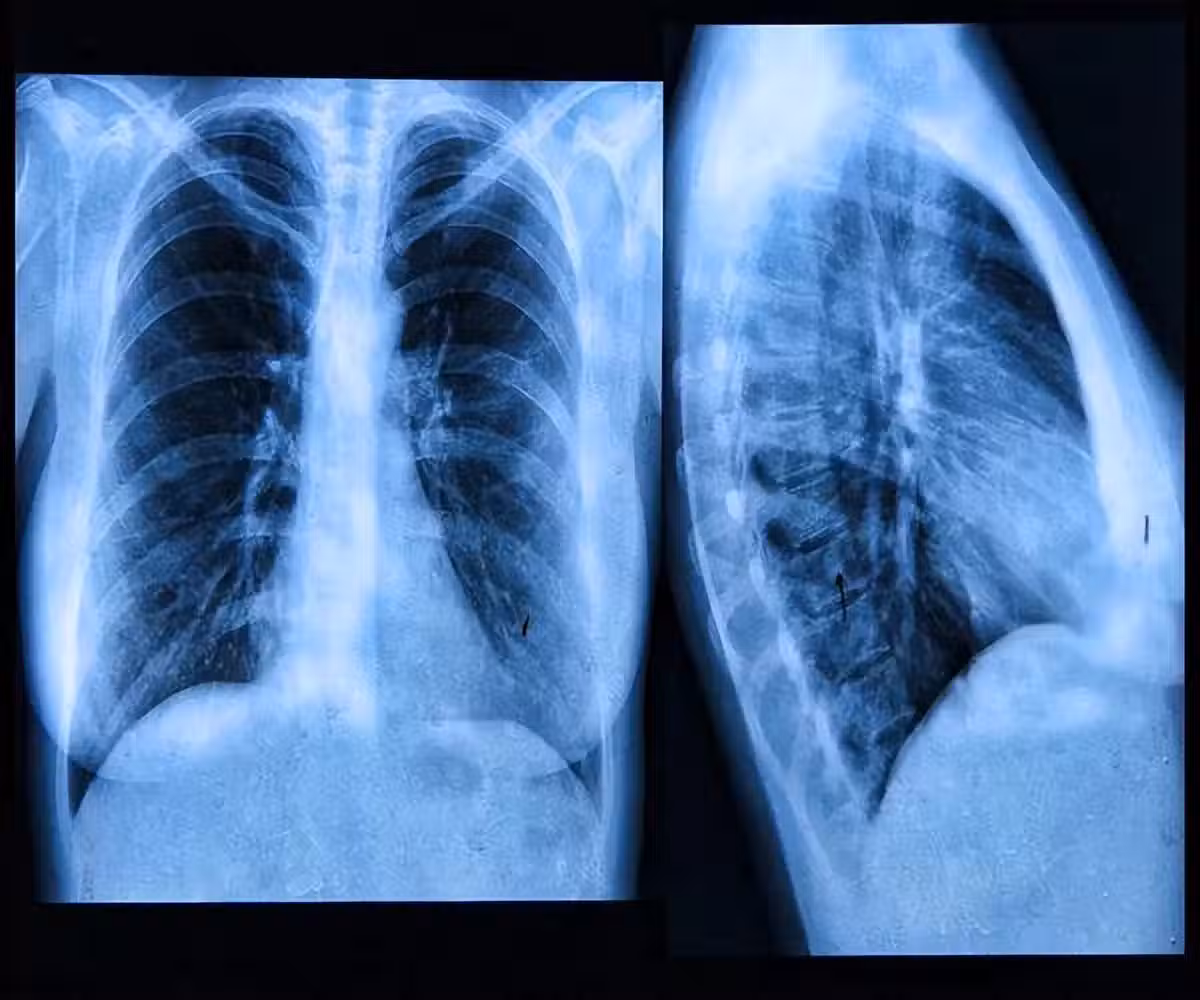

肺內有癌,腿疼告知?事實上,早期肺癌的5個跡象你更需要去關注❗

除此外,肺癌還有許多其他症狀表現,比如痰多、胸痛、食欲不振等。

肺癌對身體的傷害是不可逆轉的,因此當出現肺癌的相關症狀時,一定要及時給予對症,避免病情進一步惡化。

如果發展到了肺癌晚期,那麼即便是給予治療或化療,效果也會不盡人意。